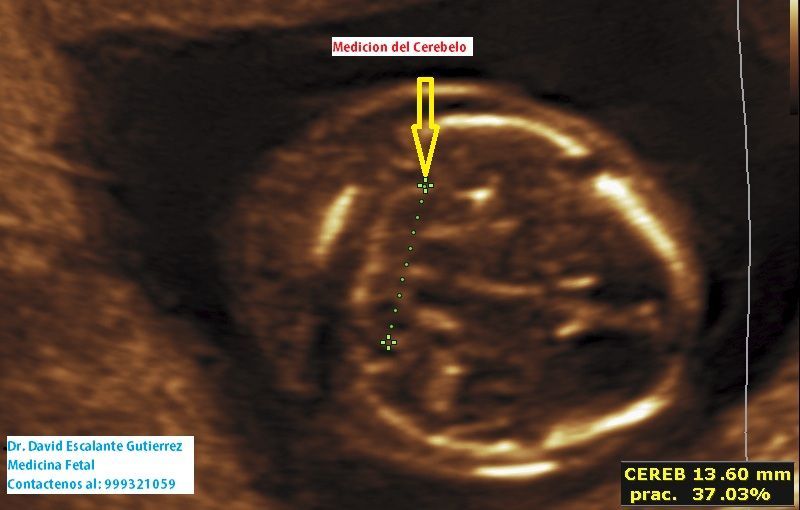

Realizamos las ecografías de viabilidad del embarazo, genética, morfológica, de bienestar fetal, ecocardiografías fetales, así como procedimientos invasivos como biopsia de vellosidades coriales y amniocentesis.